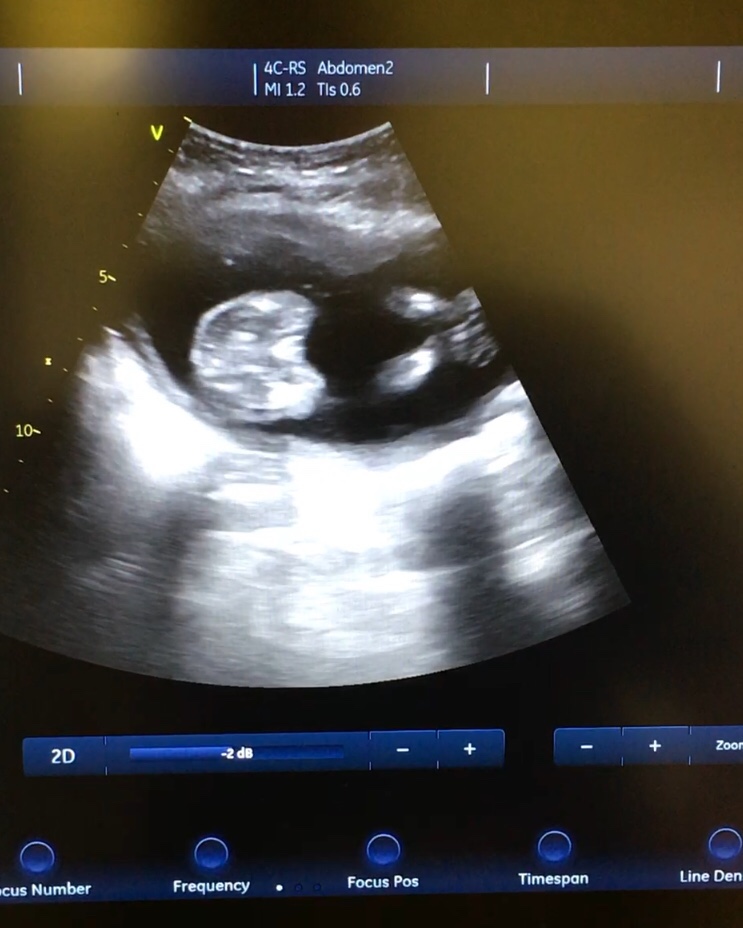

At 16 weeks we were told boy. Now at 18+4 we have been told possible swollen girl?? Is anyone able to shed any light? It won’t let me upload the video.Attachment 39493 I really want to go shopping xxAttachment 39492https://uploads.tapatalk-cdn.com/201...d91c74c9ac.jpghttps://uploads.tapatalk-cdn.com/201...118b00c07e.jpg